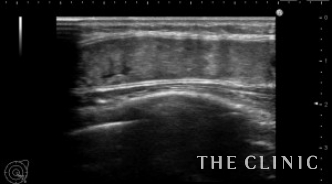

術前のエコーです。

乳腺下に充実性のしこりがあります。右はカプセル内ですがしこりは移動しませんでした。左はカプセル内を広範囲に移動します。他にも1.5㎝の小さなしこりもありこれも移動します。